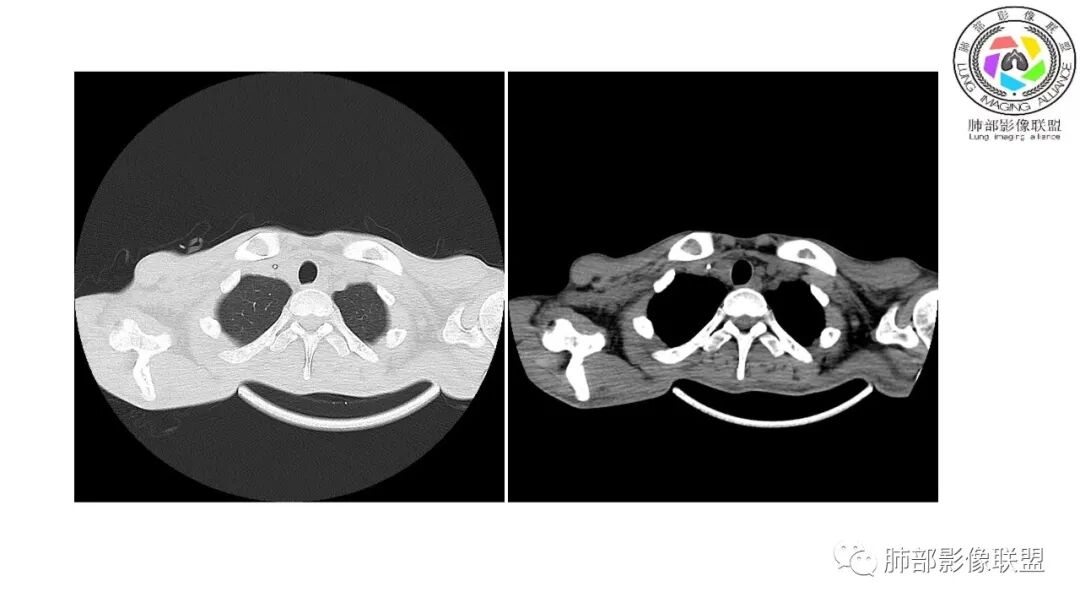

影像与临床:1.青年男性,HlV阳性,颜面部皮疹(未提供皮疹图像)、发热(高热),实验室CRP、PCT高,T-Spot阴性。2.右肺下叶空洞结节,壁厚不均,边界清楚,其内线状影,未见液平及钙化,未见卫星灶,纵隔淋巴结增大,双侧腋窝见增大淋巴结。心腔内低密度提示贫血可能。肝脾影增大,未见结节影及块影。腹膜后见多发增大淋巴结。

综合分析:本例肺部影像学改变并不具有特征性,空洞性病灶须与多种疾病鉴别,但年轻HIV阳性患者,高热,皮疹,肝脾增大,纵隔、腋窝、腹膜后见多发增大淋巴结等都强烈提示马尔尼菲篮状菌感染的可能性。